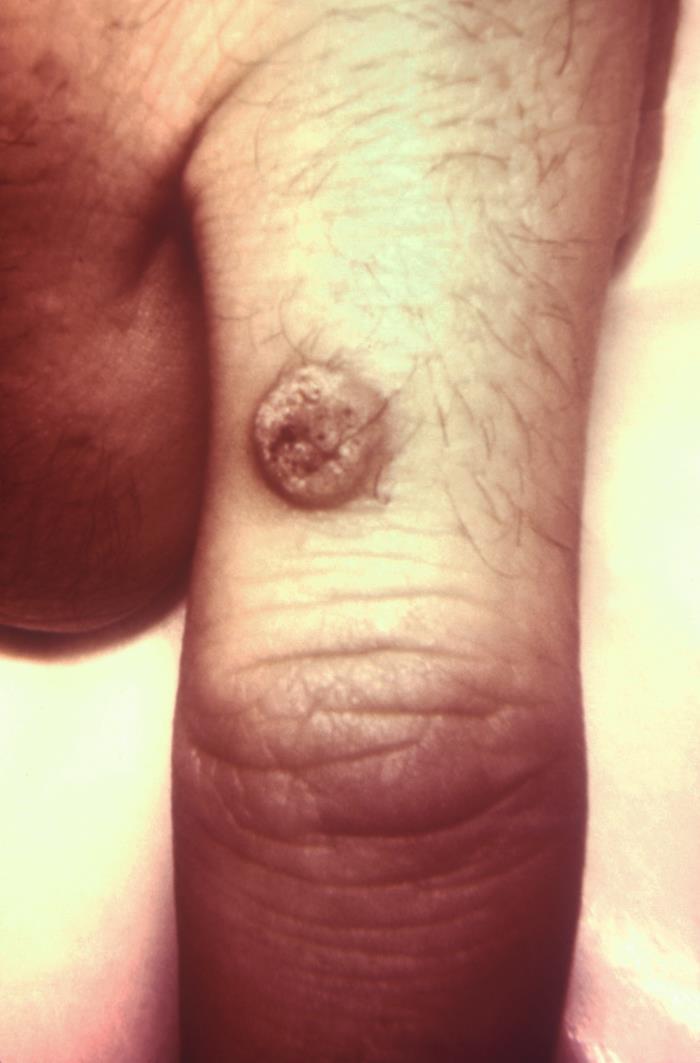

- Plantar warts (verruca plantaris):

- The second most common type of wart.

- Most common in adolescents/young adults.

- Upon paring down [Fig 2], thrombosed capillaries are distinguished from callus.

Plantar wart

Upon paring down lesion, evidence of thrombosed capillaries distinguish from callus. Also, calluses tend to be non-painful.

Source: Wikimedia, Δρ. Χαράλαμπος Γκούβας